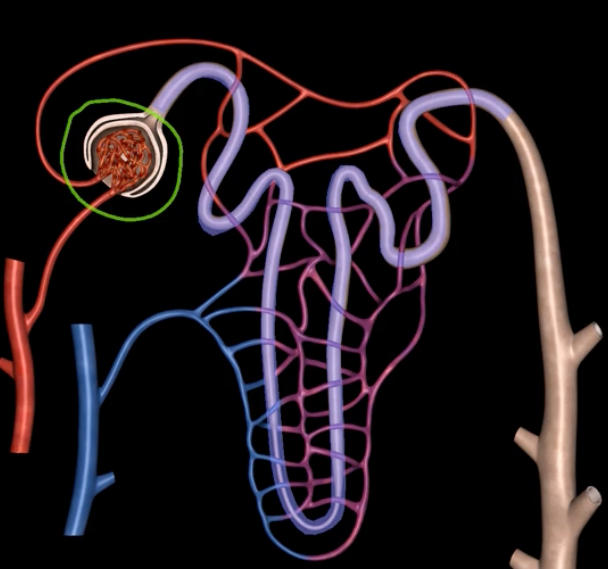

green: renal corpuscle

purple: renal tubule

green:

purple:

blue: glomerulus

orange: Bowman’s capsule

blue:

orange:

juxtaglomerular structure

juxtaglomerular (granular) cells, modified smooth muscle cells, release renin in response to signals from macula densa

yellow arrow

macula densa

blue arrow

extraglomerular mesangial cells

green arrow

macula densa, modified columnar epithelium

juxtaglomerular cells

If macula densa detect a decrease in ion concentration, then they stimulate _____ cells to release renin which actives RAAS